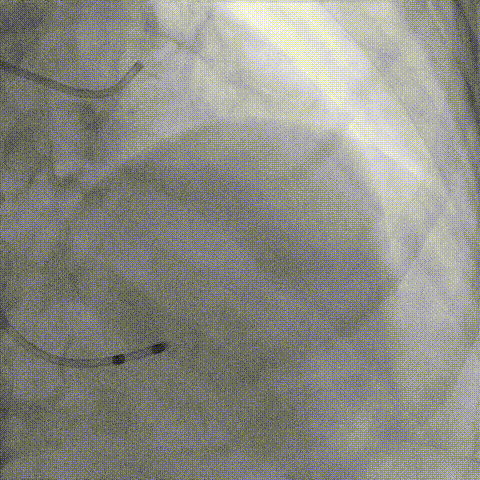

冠脉造影